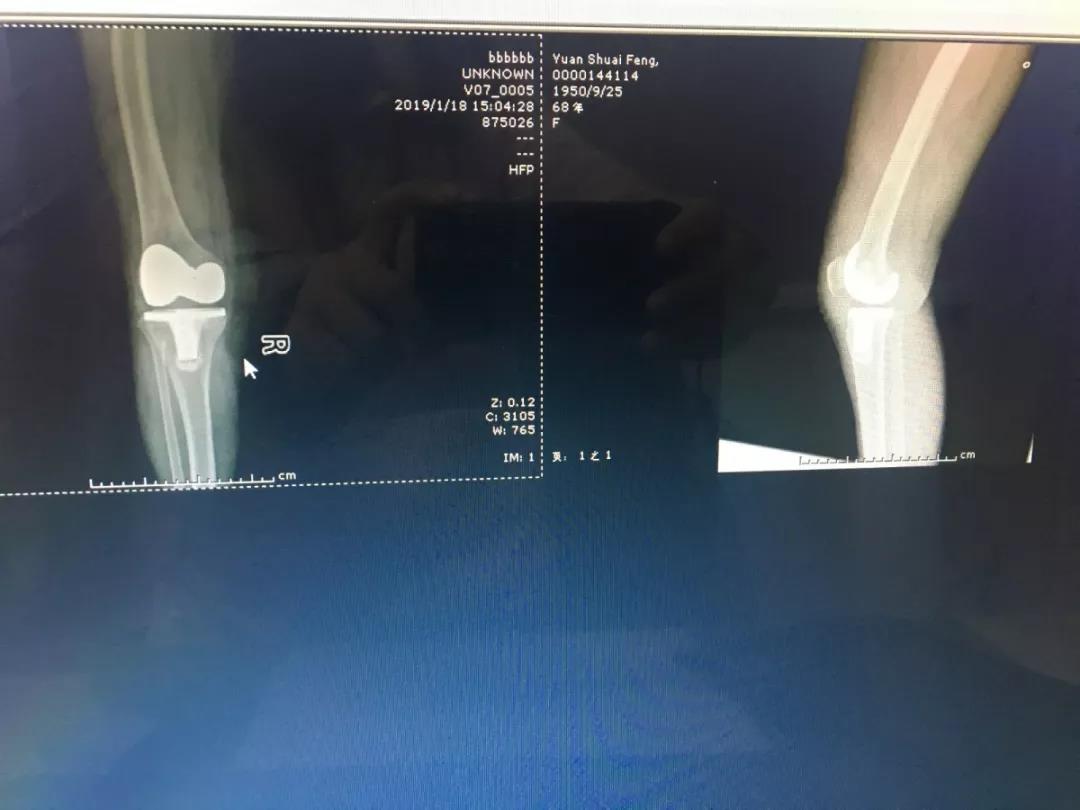

经检查,袁大妈患上的是“双侧膝关节退行性骨关节炎”,尤其是右膝病变的最为严重。这是由膝关节退行性病变引起的一种疾患,如果再不进行手术,老人将无法行走,且容易引起身体其他器官功能的下降。杨主任决定为袁大妈进行全膝关节置换术,以帮助其恢复行走能力。家属对杨主任及骨科团队十分信任,听完杨主任制定的诊治方案后当即签下了手术同意书。

经过1个多小时的手术,杨主任带领的骨科团队成功完成了袁大妈的右膝关节置换。术后,丁红护士长带领的护理团队对袁大妈精心护理,及时为她进行康复训练,术后不到3天,袁大妈就能下地轻松行走了。家属看到老人恢复的这么快,都非常激动,连连赞叹现代医疗技术的高超,袁大妈脸上也都是喜悦之情,说这是她收到的最好的新年礼物了。

术后不到3天,老人即可下地行走